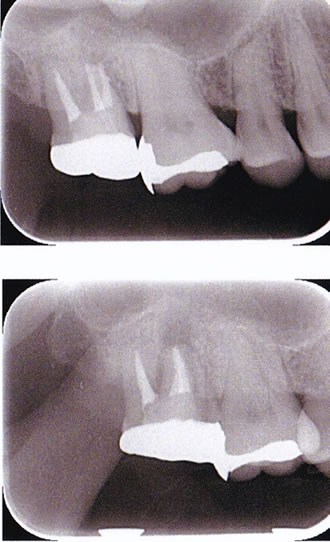

After

根管内の感染源を完全に除去し、緊密に封鎖しました。

【根管充填】

欧米の根管治療の専門医の多くがおこなっているcontinuous wave condensation technique(通称CWCT)で行いました。根管を3次元的にすき間を極力なくして根充剤(根管治療の最後につめる薬剤)を緊密に圧入していきます。従来の根充法より格段にむずかしいテクニックですが、その分、より確実な根管充填ができます。